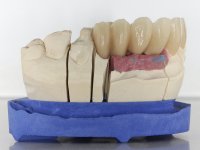

A temporary acrylic bridge made in the laboratory with 7 elements was made, with teeth 11,21, 25 and 26 as pillars. The old bridge was removed and tooth 24 was extracted. The provisional bridge after relining was cemented in the mouth. Two implants were placed in the teeth 22 and 24 and 3 months after this intervention an impression was made to make a temporary bridge screwed over the implants and cemented to the teeth. The bridge was placed in the mouth and teeth 25 and 26 were extracted. 3 months later, surgery was performed to fill the maxillary sinus and 6 months later the implant was placed in the location of tooth 26. After osseointegration of this implant, the final impression was made for the final work. The bridge over the implants was permanently screwed on and the bridge over the teeth was cemented with resin-reinforced glass ionomer cement.